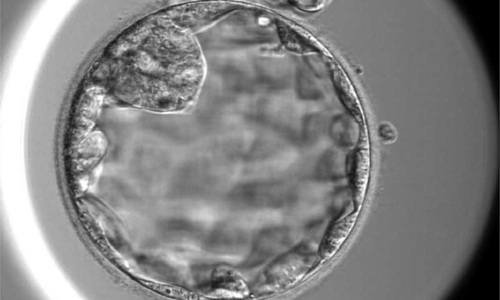

I underwent in vitro fertilization and produced 5 embryos, but 4 failed to develop. The one day 5 embryo transferred did not result in pregnancy. Is there a way to improve embryo quality? (Linh, age 33)

My husband and I received embryo biopsy results showing aneuploid abnormalities in multiple chromosomes (3, 4, 9) and a 30% mosaicism rate. Should such an embryo be transferred to the uterus? (Linh, Lam Dong)

Nguyet, 33, carrying the thalassemia gene, underwent in vitro fertilization and produced a single embryo with a 30% chromosomal abnormality, successfully giving birth to a healthy child.